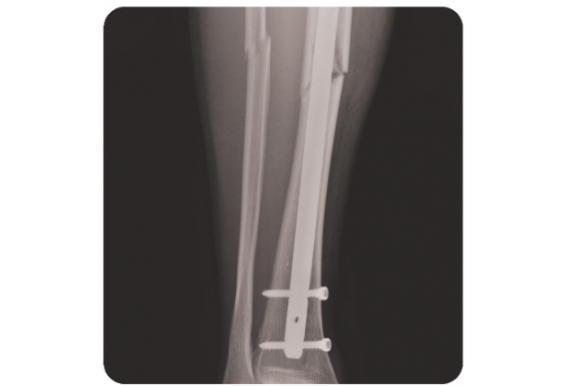

MSP: Multi-fix ORTHOTECH femur nail & plate system

Xuất xứ: Hàn Quốc

Ứng dụng:

Chỉ định các trường hợp gãy xương đơn ở xương đùi và xương cẳng chân

- Vật liệu: Titanium nguyên chất Gr4

- Vít:

Ø4 vít khóa vỏ xương có ren

Ø3.5 vít khóa vỏ xương

Ø3.5 vít vỏ xương